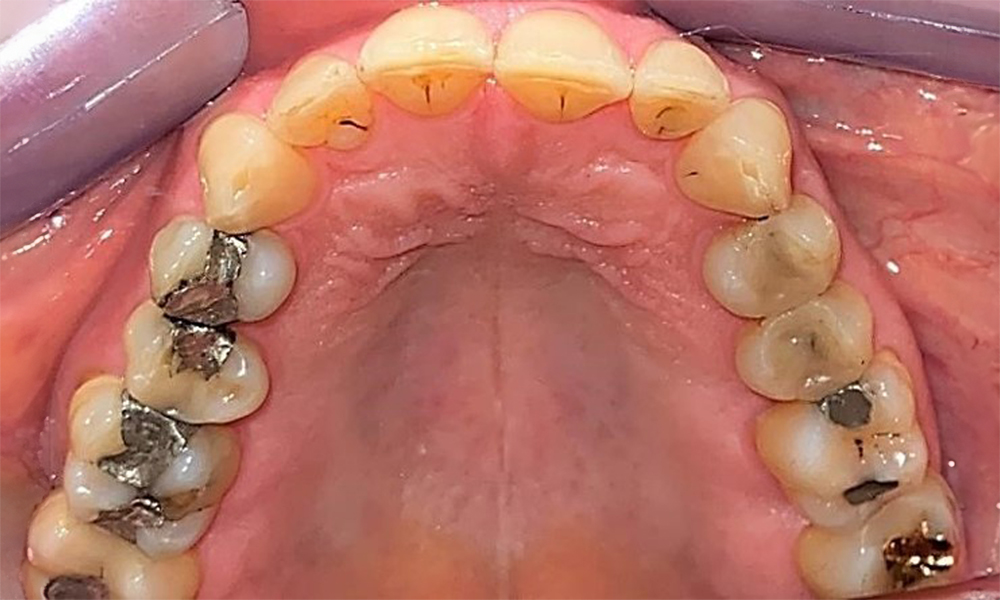

The patient has a full dentition with 28 teeth, which includes amalgam and composite fillings in the molar and premolar regions. There is a visible clinical marginal gap present on tooth 14. Tooth 27 has an adequate gold inlay. There are also generalized attritions and abrasions. (Fig. 2, Fig. 3, Fig. 4, Fig. 5, Fig. 6)

The patient has stage II, grade B periodontitis (5). At 1 to 3 mm, the clinical probing depths were within the physiological range. Localized probing depths of 5 mm were observed on the mesiopalatal aspects on both 17 and 27. There are generalized recessions of 1–3 mm with partial loss of the interdental papillae (Fig. 2, Fig. 3, Fig. 4)